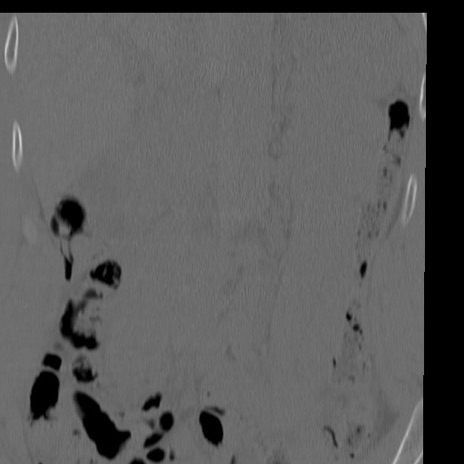

症例3 腰椎CT(冠状断像)

腰椎CT